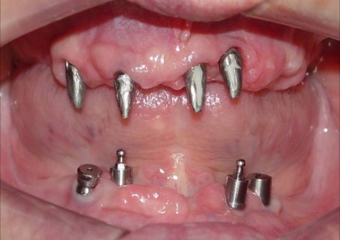

Imagens após remoção dos dentes e do implante comprometido